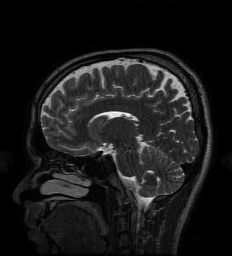

5.6 MRI Experiments

| Original/Mask | PNN | NN | MoDL | GDN2 | GDN1 | TNRD | TV |

| PSNR (dB) | 34.95 dB | 33.09 dB | 34.09 dB | 33.18 dB | 31.37 dB | 32.39 dB | 32.29 dB |

| Test Time (sec) | 16.3 sec | 5.5 sec | 14.3 sec | 5.7 sec | 3.1 sec | 4.0 sec | 349.2 sec |

In this section we provide results of multi-coil MRI reconstruction from undersampled measurements. Full training and test data is the data used for the experiments in [47], consisting of 12-coil Cartesian sampled k-space data of dimension with known coil sensitivity maps. The size of the training set is 360 such acquisitions across 4 subjects, with testing being performed on 40 images from one, separate subject who was not used for training. The sum-of-squares reconstruction is treated as ground truth. Further details of the data acquisition can be found in [47].

All experiments are for 4 undersampling, although we differ from [47] in that we train on a fixed k-space undersampling mask. The undersampling mask is fully sampled in the center 0.15 fraction of frequencies, with the remaining frequencies being sampled according to a random Gaussian pattern. The mask is visualized in figure 10.

For the MRI experiments we follow the precedent set by [47] in our choice of learned component, using only a simple five-layer convolutional network with 64 filters per layer and ReLU nonlinearities for all architectures other than TNRD. The TNRD architecture follows the architecture proposed in [33]. The Neumann network results presented here are for the preconditioned Neumann network (PNN), and the number of blocks for GDN, PNN, MoDL, and TNRD is fixed to be 5. The preconditioning operator in PNN is implemented through 10 conjugate gradient iterations, identically to [47]. We compare to GDN with the same initialization as NN (GDN1) and as PNN (GDN2) to study the effect of different initializations on GDN.

We observe that unrolled optimization approaches are advantageous in this setting compared to the more traditional TV-regularized reconstruction. Preconditioning, both to improve initialization as in GDN2, and incorporated into the architectures, as in PNN and MoDL, improves PSNR significantly in this setting.

A major benefit of learned reconstruction methods is their test time, which is displayed beneath the method name and PSNR in Figure 10. We note that all learned approaches reconstruct an order of magnitude faster than the agnostic TV approach. Although preconditioning incurs an additional cost in terms of test time, the performance increase is substantial for MoDL and PNN.